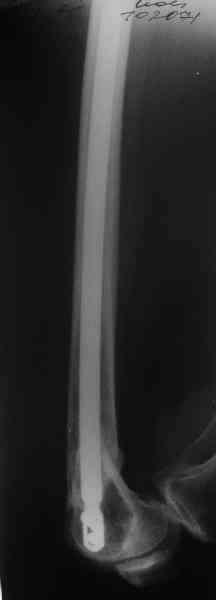

Re: Перелом диафиза и мыщелка бедра

В приложении функциональные снимки в 3 мес. и в 1 год.